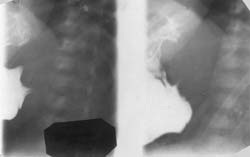

При менее выраженном стенозе удается получить рентгенологическое изображение всего пилорического канала, который значительно удлинен — до 10–15 мм, а иногда и более, при нормальной длине его 2–4 мм. Данный симптом носит название «усика» или «жгутика». В большинстве случаев этот признак является единственным, а иногда он может возникать вслед за клювовидным заполнением начала пилорического канала (Рис. 2).

[Увеличить]

Рис. 2. Больной В., 1 мес. Врожденный пилоростеноз. Симптом «усика» или «жгутика». Вторичный гастроэзофагальный рефлюкс.